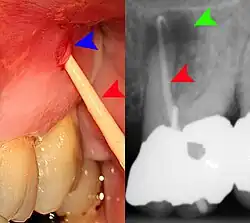

Sometimes the symptoms reported in the history are misleading and point the examiner to the wrong area of the mouth. For instance, sometimes people may mistake pain from pulpitis in a lower tooth as pain in the upper teeth, and vice versa. In other instances, the apparent examination findings may be misleading and lead to the wrong diagnosis and wrong treatment. Pus from a pericoronal abscess associated with a lower third molar may drain along the submucosal plane and discharge as a parulis over the roots of the teeth towards the front of the mouth (a "migratory abscess"). Another example is decay of the tooth root which is hidden from view below the gumline, giving the casual appearance of a sound tooth if careful periodontal examination is not carried out.

Decay (green) with apical abscess (blue) -

Gutta-percha point indicating abscess origin